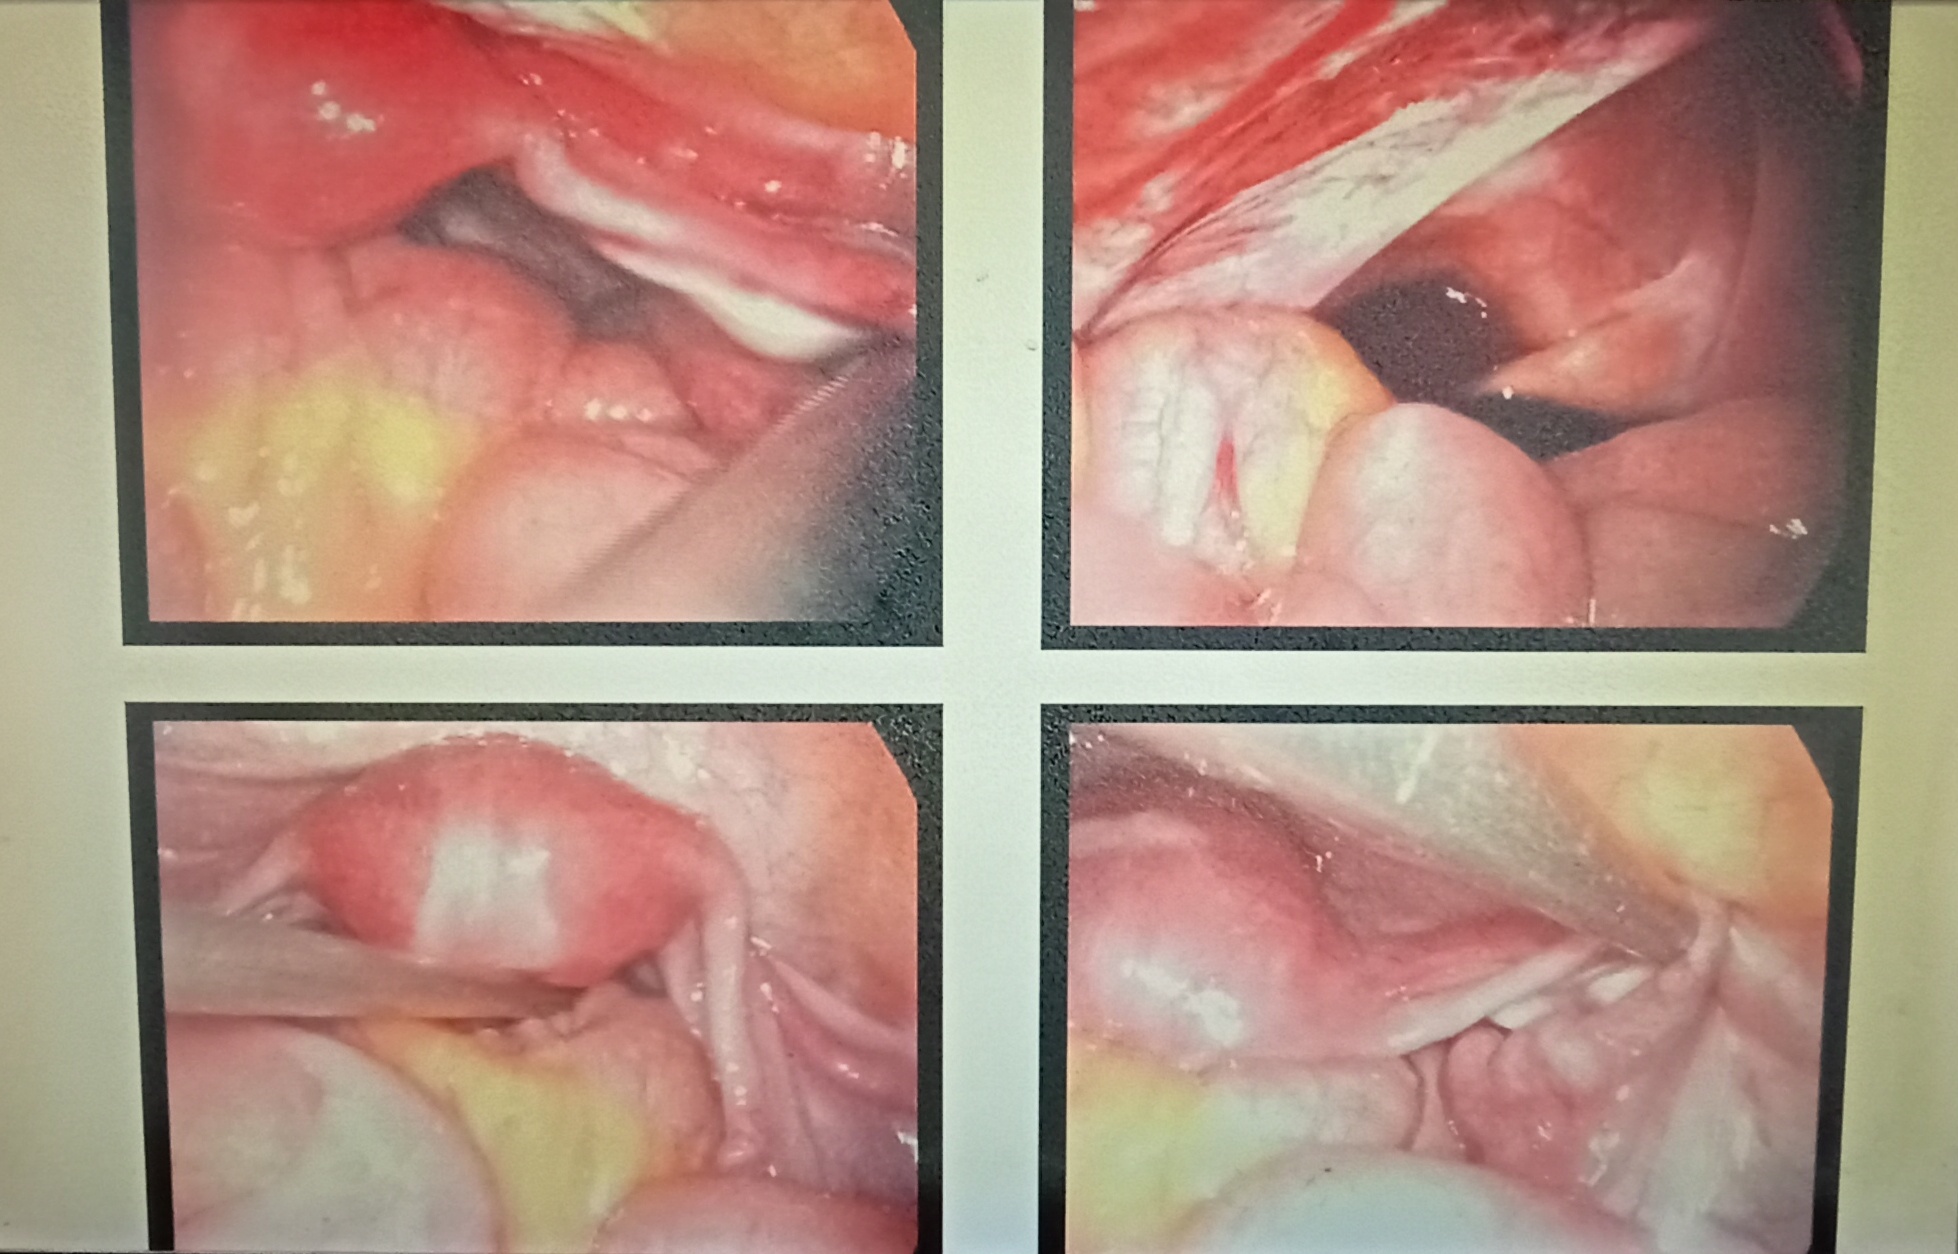

History of this patient : She is 26 years old married since 5 years and irregular periods, case of infertility. We have done the laprascope for this patient. After finishing the procedure,advice for found the AMH LEVEL and then further treatment of ivf because both ovaries are small in size.